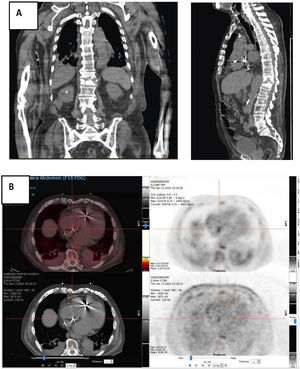

18F-FDG PET-TAC que objetivó actividad metabólica en columna dorsolumbar D11-D12 y en región distal del cable del marcapasos, a nivel del septo interauricular (fig. 1).

An 87-year-old patient with a pacemaker due to sinus disease was hospitalized due to spondylodiscitis by Staphylococcus (bone biopsy). Infection of the electronic device was suspected, and repeated blood cultures were all positive. Echocardiography did not detect vegetations, but PET_CT showed positive images on wires. The complete device was then extracted, and lead cultures confirmed the diagnosis, with total recovering of patient.